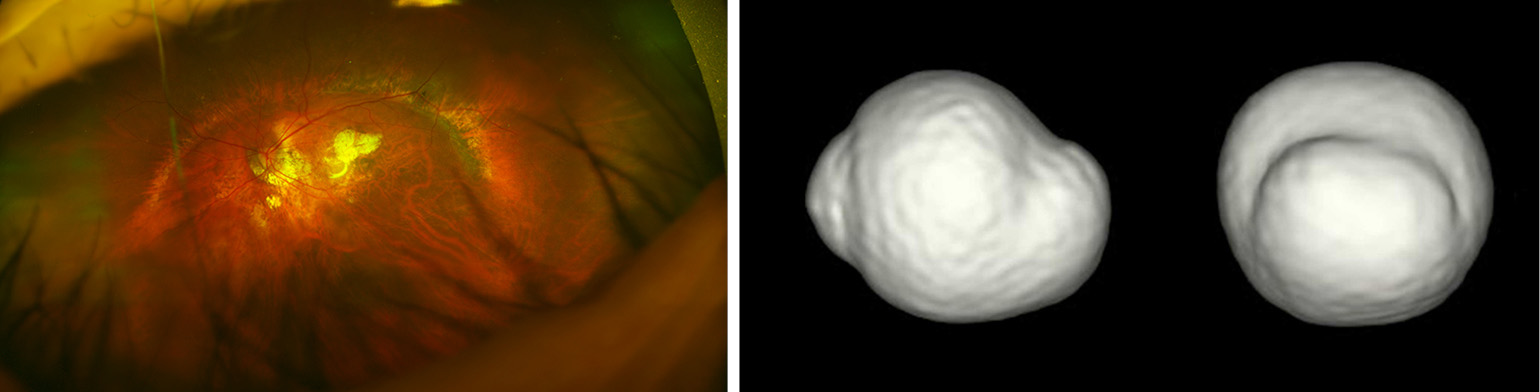

Myopic CNV and CNV-related macular atrophy (Figures 5,6)

figure5

figure6

Myopic CNV is a major sight threatening complication of PM. It is the commonest cause of CNV in individuals aged below 50 years, and the second commonest cause of CNV overall (35,36). Myopic CNV tends to be small and thus about 20% of them was extrafoveal (37). Most of them are type II CNV, above the RPE. In natural course as well as after treatment, myopic CNV goes through three phases; active phase, scar phase, and atrophic phase (also known as myopic CNV-related macular atrophy) (Figure 7).

However, it is not fully clarified whether anti-VEGF treatments are effective for late complications occurring around the scarred myopic CNV; which is CNV-related macular atrophy. Recent study using swept-source OCT by Ohno-Matsui et al. (41) showed that CNV-related macular atrophy was also an enlarged hole of BM around the CNV (Figure 5). To improve the long-term outcome of anti-VEGF therapies for myopic CNV, the prevention of BM hole enlargement around the CNV is necessary.